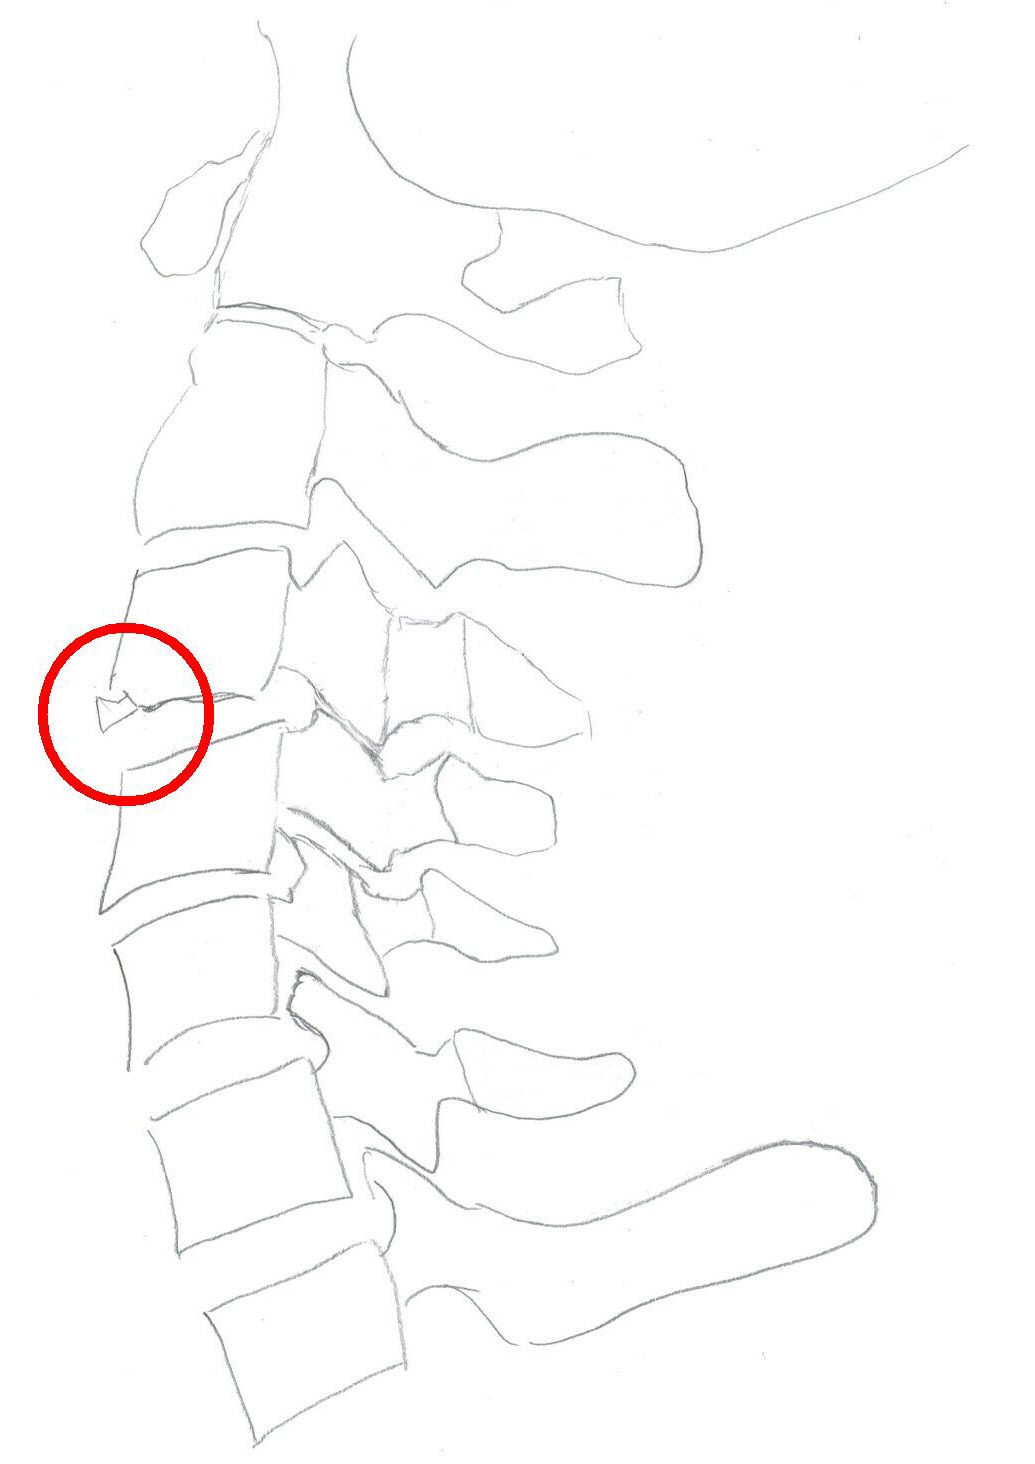

Typiskt äldre patient med degenererad halsrygg som fallit på pannan berusad. DT med diskreta fynd, kan vara helt normal, visa extensions teardrop (se bilder nedan) eller distraktion i disk. Kan vara mycket instabil.

Teardropfrakturer